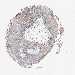

CANCER SKIN CANCER Show tissue menu

Basal cell and squamous cell cancer

SKIN CANCER - Protein expressioni

A mouse-over function shows sample information and annotation data. Click on an image to view it in a full screen mode. Samples can be filtered based on level of antibody staining by selecting one or several of the following categories: high, medium, low and not detected. The assay and annotation is described here.

Each image is clickable and will lead to virtual microscopy that enables deeper exploration of all samples and also displays staining intensity scores, fraction scores and subcellular localization as well as patient and tissue information for each sample.

Antibody HPA029855

Antibody HPA029856

Antibody CAB026343

Basal cell carcinoma

Squamous cell carcinoma, NOS

Squamous cell carcinoma, metastatic, NOS